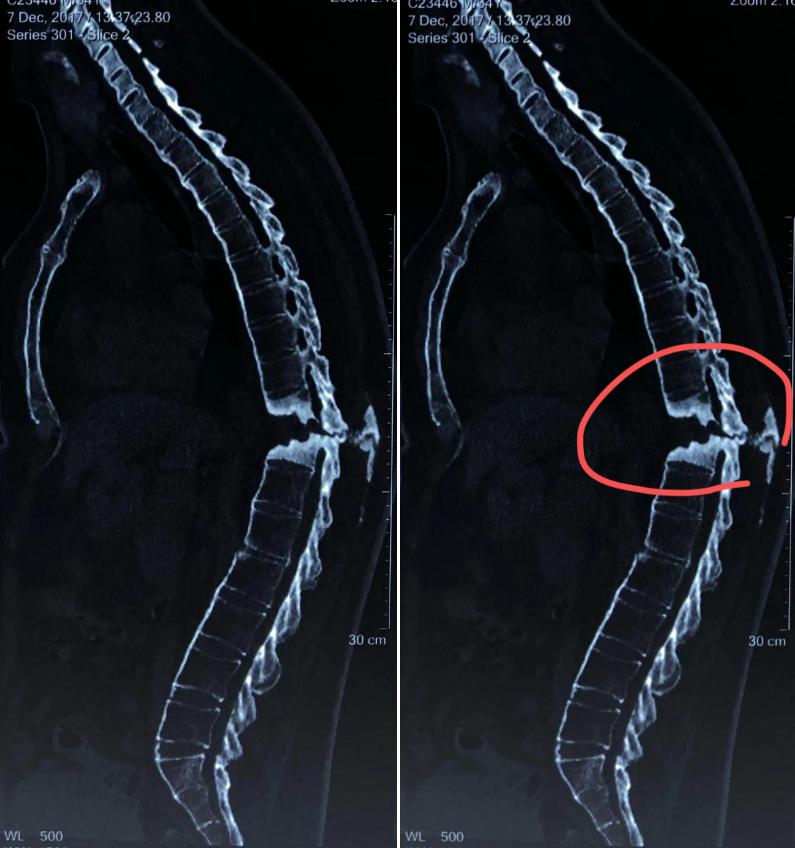

看见上面这张X线片,相信没有医学背景的人也能一眼看出,脊柱在红圈部分的椎体被破坏,好像被什么东西侵蚀了一样,快要马上断开了似的,十分凶险。而这张片子的主人——乌先生(化名)也特别让我记忆犹新,怎么回事?这就要说到三年前刚遇见他时的事情了。

我仔细地观察了吴先生的影像学片子和其他检查单,并给他进行了详细地查体,怀疑他是强直性脊柱炎脊柱骨折。于是建议他进一步做相关检查,最后排除了肿瘤、结核可能,并发现他的HLA-B27呈阳性,X线显示两侧骶髂关节融合,符合强直性脊柱炎表现。而从他的影像学片子上可以观察到,胸11椎体出现溶骨性腔隙,脊髓已经受到压迫,考虑是强直性脊柱炎引起的Anderson病变,并且有骨质疏松问题。而这种情况基本上保守治疗无效,于是建议他进行抗骨质疏松治疗,并尽快进行手术治疗。

脊柱真的断了?这种Anderson病变病较罕见!

吴先生的下肢问题终于找到了真正的病因,他决定积极配合手术治疗,但对自己的病情仍有一定疑问。“这个Anderson病变是个什么病?根本没听过。”、“我自己看片子,这里的脊柱是不是真的断了?手术后还能长回去吗?”……

其实,Anderson病变是强直性脊柱炎比较少见的并发症,也叫作强制性脊柱炎应力骨折。它是强直性脊柱炎患者出现的椎间盘-椎体溶骨性病变,可累及脊柱的三柱,多发生于胸腰段。这种骨折的发病诱因常常是一些轻微外伤或无明显外伤造成。骨折发生后,由于强直性脊柱炎患者的骨质疏松也比较严重,导致骨折久久不愈,形成假关节强直性脊柱炎骨折。

那脊柱出现这样的腔隙是不是就是脊柱断开了?事实上,Anderson病变引起这样的骨质缺损,被破坏的部分将由血管纤维组织和纤维软骨填补,并不是说脊柱就完全断开,腔隙里面是空的。